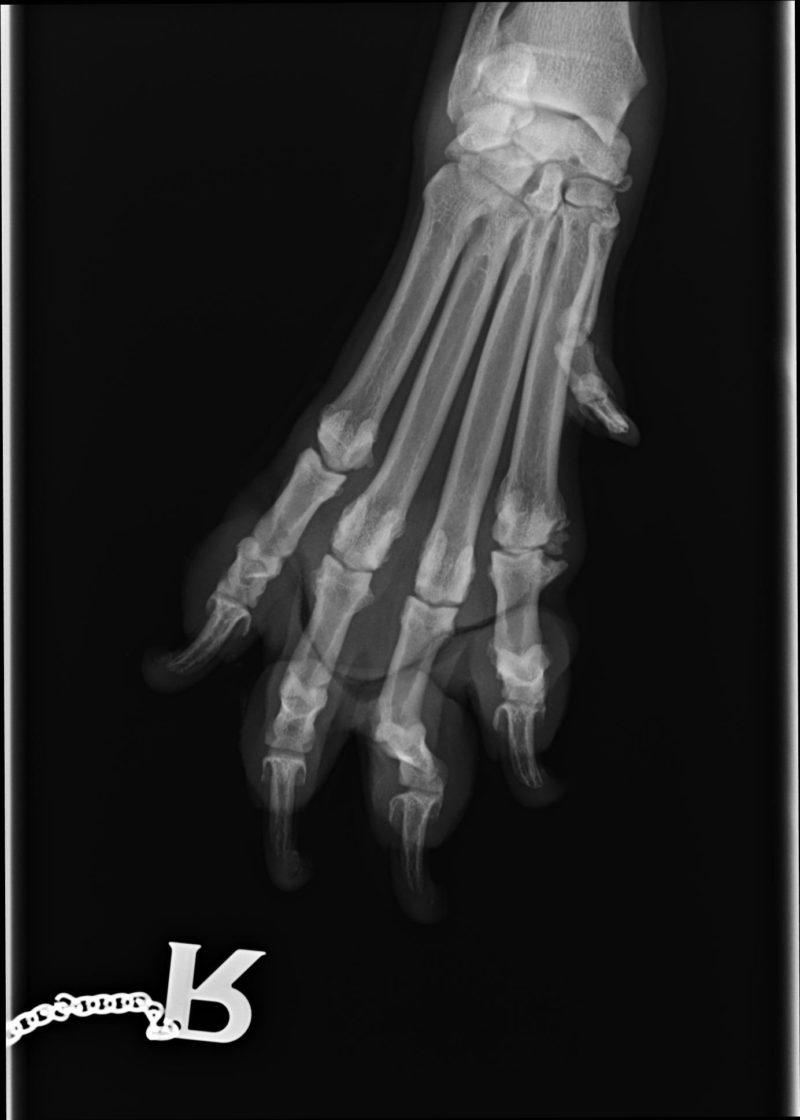

Bei genauerer Untersuchung des gesamten Bewegungsapparates im Gehen, Traben und auch durch Abtasten wurde allerdings schnell klar, dass der rechte Ellbogen nicht Bonnies einziges Problem war. Bonnie ging beim Vorlaufen (Gangbildanalyse) insgesamt recht steif, vorne übermäßig breit, hinten sehr eng und mit der Hinterhand nach rechts versetzt. Die Lahmheit zeigte sich im Trab deutlicher als im Schritt, beim Abtasten reagierte Bonnie druckschmerzhaft am rechten Ellbogen, an einzelnen Zehengelenken vorn beidseits, an den Schultergelenken, der gesamten Wirbelsäule, der rechten Hüfte und geringgradig an beiden Kniegelenken. Alle auffälligen Stellen wurden daraufhin geröntgt. Röntgenologisch fanden wir bei Bonnie, entsprechend der Schwere der Befunde absteigend geordnet:

- Zehengelenksarthrosen vorn beidseits